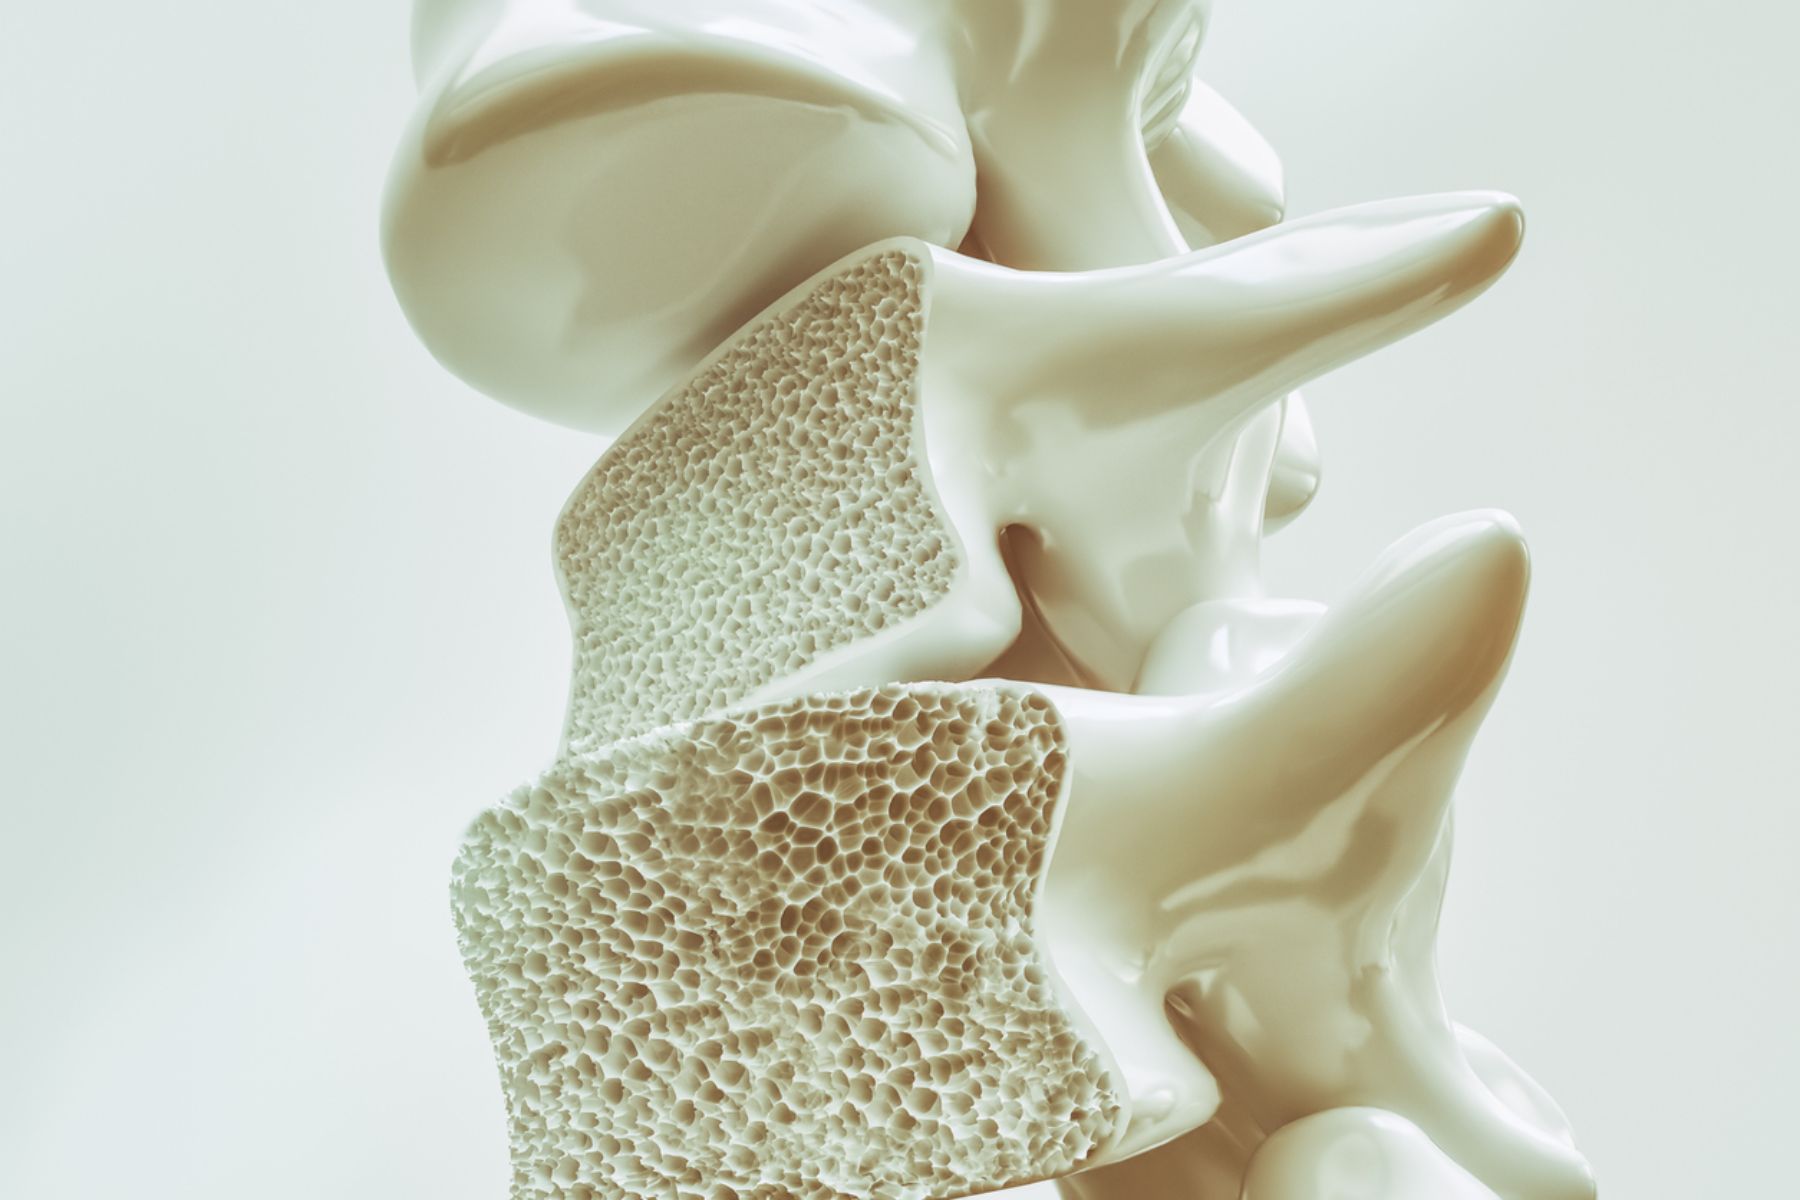

Osteoporosis

A bone disease causing reduced bone density and increased fracture risk. Early detection and proper treatment help strengthen bones and prevent fractures.